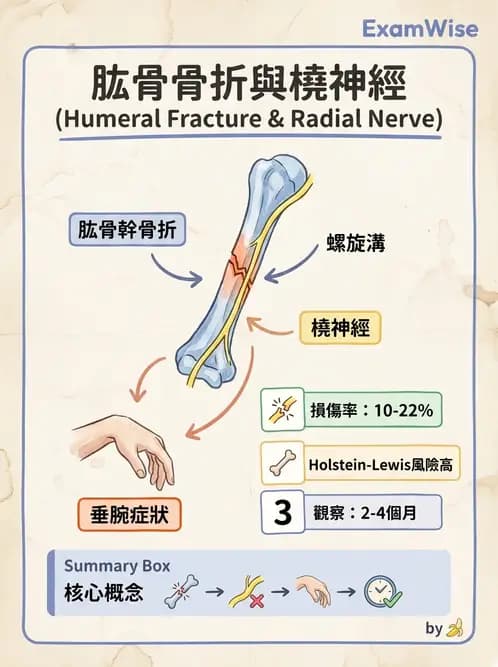

肱骨(humerus)幹部骨折(humeral shaft fracture)與橈神經(radial nerve)損傷的解剖關係。橈神經在肱骨中下段行走於「螺旋溝(spiral groove / radial groove)」,此部位的骨折是最常見的周邊神經合併損傷之一,臨床表現為垂腕(wrist drop)。

此為左上臂前後位 X 光片(標記「L ADH」),顯示左肱骨全長。白色箭頭指向肱骨幹中下 1/3 交界處,可見骨皮質連續性中斷,呈橫向或斜向骨折線,為典型的肱骨幹骨折。此骨折位置正好落在螺旋溝所在區域——橈神經從肱三頭肌兩頭之間繞行至肱骨後外側,在中下段貼緊骨面走行,再穿越外側肌間隔進入前室。箭頭指示的骨折線即位於橈神經最易被牽拉或夾壓的「Holstein-Lewis 骨折」好發部位。

(B) 橈神經(radial nerve) 橈神經(C5–T1)自腋窩後方沿肱三頭肌長頭與外側頭之間向下,繞行至肱骨後側螺旋溝,在中下 1/3 交界穿過外側肌間隔